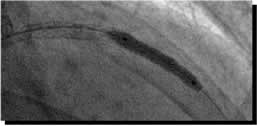

![]() Flexicut M |

![]() POBA 3.5mm@16atm |

![]() Stent 3.5mm/18mm |